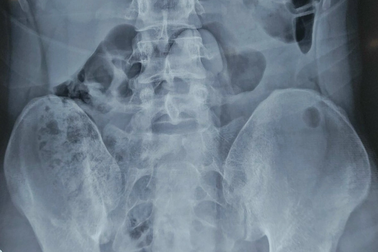

Dương vật “khủng” kẹt trong hậu môn nam thanh niênNhập viện trong tình trạng đau tức vùng hậu môn, qua kiểm tra hình ảnh, bác sĩ phát hiện dương vật giả có chiều dài 18cm đang nằm trong trực tràng nam thanh niên.

Sextoy kẹt trong trực tràng người đàn ông khi đang "tự sướng"Đang "tự sướng" thì dương vật giả lọt vào trực tràng khiến người đàn ông phải nhập viện cấp cứu. Sau nỗ lực thủ thuật các bác sĩ đã lấy được sextoy ra ngoài giúp bệnh nhân tránh cuộc mổ lớn.

TPHCM: Cấp cứu nam thanh niên bị kẹt dương vật giả dài 25cm trong vùng kínNam thanh niên sử dụng đồ chơi tình dục là dương vật giả ở nhà nhưng không may bị mắc kẹt, khiến vùng bụng dưới, hậu môn vô cùng đau đớn.